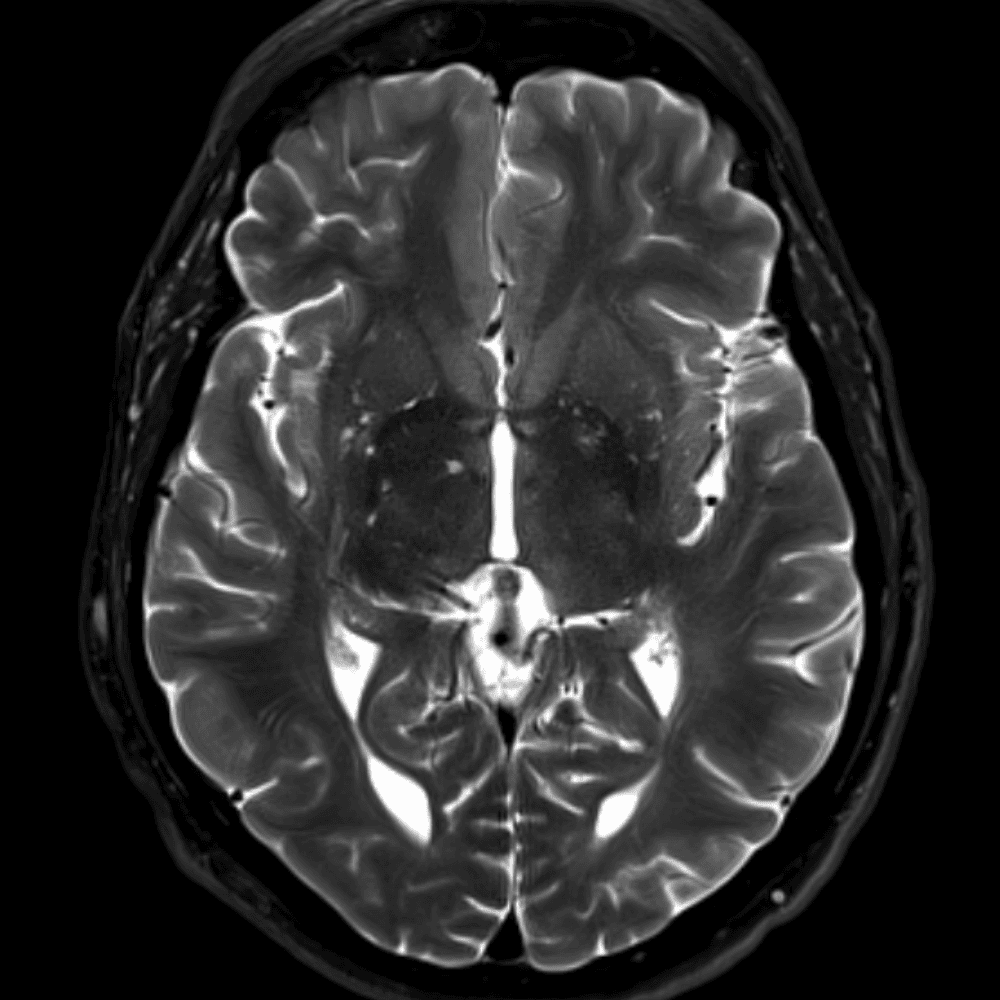

๋‹น์ง ์‹œ ํ”ํžˆ ๋ณผ ์ˆ˜ ์žˆ๋Š” ์‚ฌ๋ก€์˜ ์ „ํ˜•์ ์ธ ์˜ˆ๋ฅผ ํฌํ•จํ•ฉ๋‹ˆ๋‹ค.

39 ์‚ฌ๋ก€